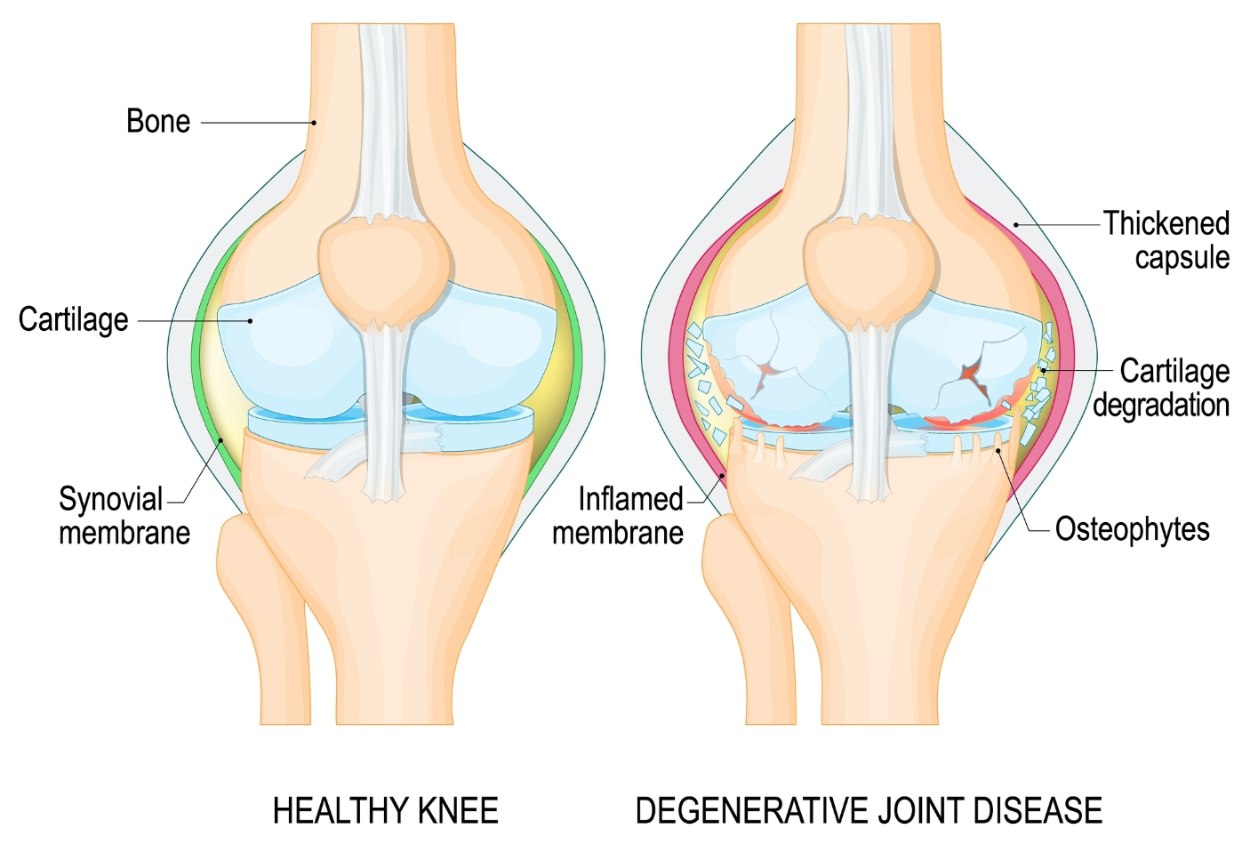

Severe knee pain from arthritis or joint damage can make everyday tasks like walking, climbing stairs, or even resting difficult.

Arthritis is the most common cause — as the knee cartilage wears away, the joint becomes stiff, swollen, and painful, eventually limiting your ability to walk and stay active.